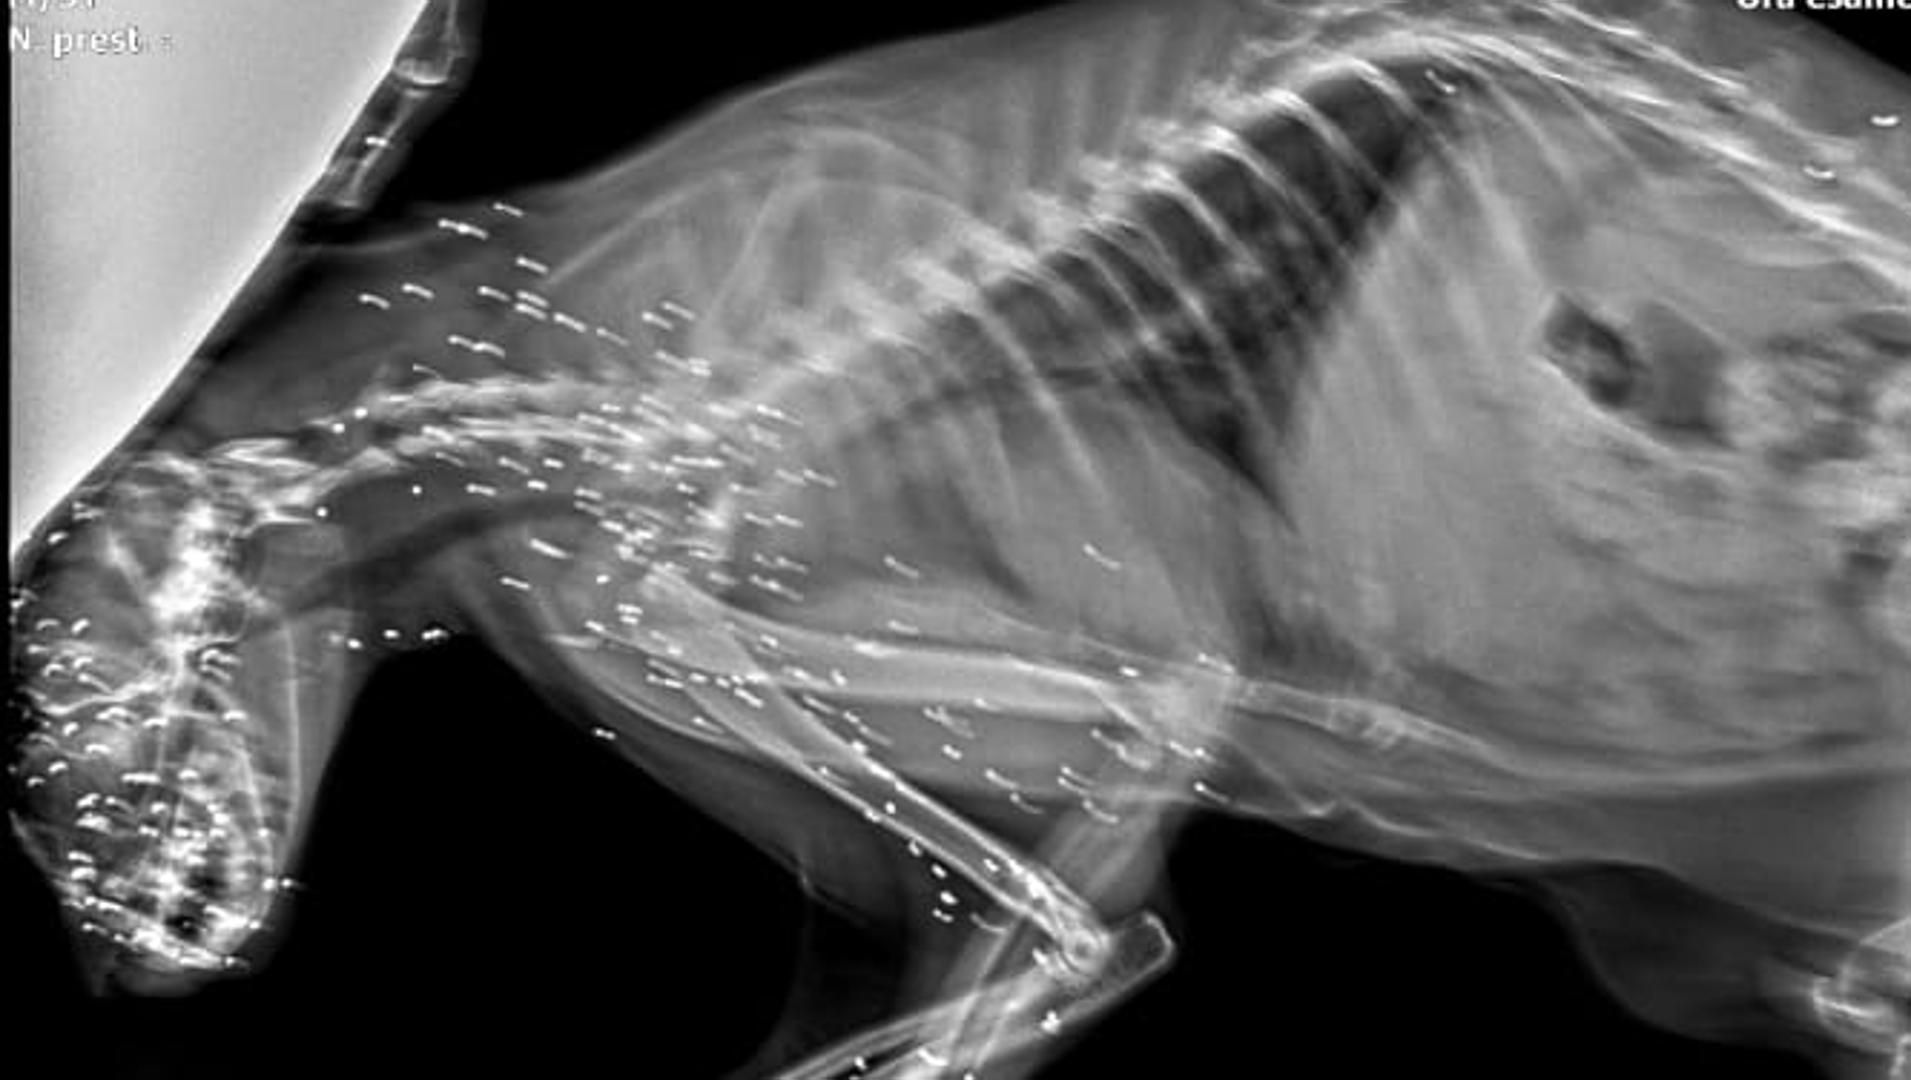

Secondo quanto denunciato dalla Lega per l’Abolizione della Caccia – sezione di Lecco, il fatto risale a due settimane fa. Il gatto è stato soccorso e trasportato d’urgenza dal veterinario, dove la radiografia ha chiarito la natura delle ferite: non un incidente, ma colpi d’arma da fuoco indirizzati volontariamente verso un animale indifeso appartenente a una colonia riconosciuta e tutelata. L’associazione parla di un episodio “vile” e porta l’attenzione sui rischi collegati alla presenza di persone armate nei boschi.